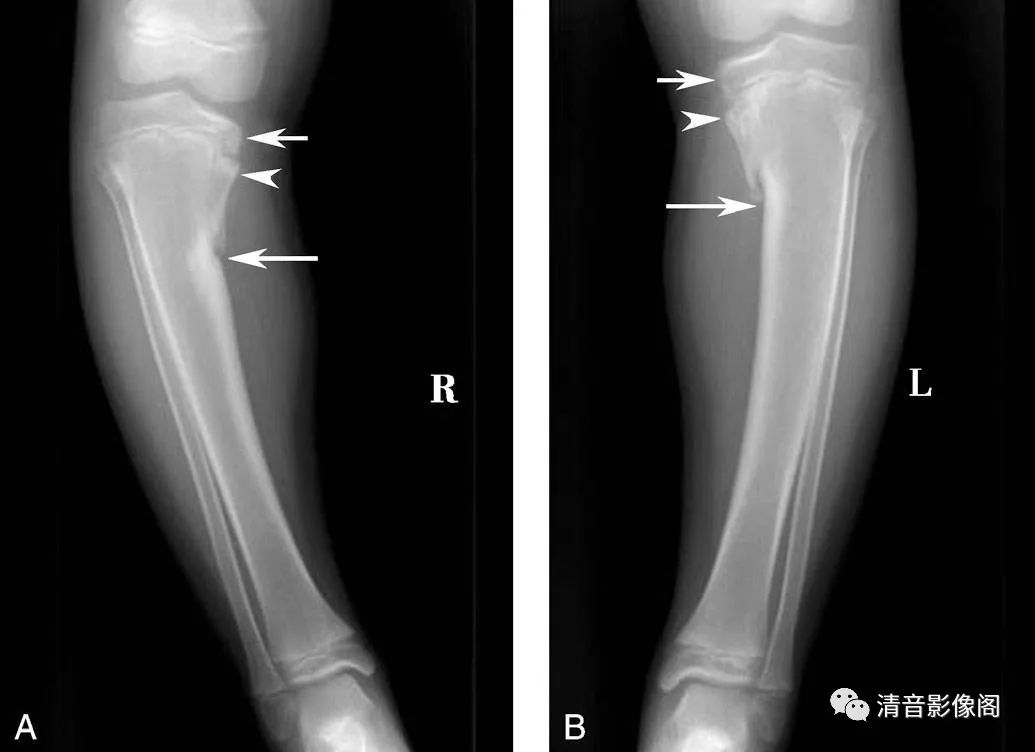

胫骨畸形性骨软骨病

A、B. 双侧胫腓骨正位X片。男,10岁。两侧胫骨内侧骨骺发育不良(短箭),累及干骺端(箭头),形成内翻畸形(长箭)。与局灶性纤维软骨发育异常的区别在于后者多单侧发病,边界清晰,位于胫骨上内侧皮质下,骨骺正常。